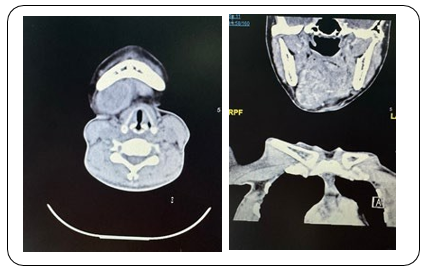

A 43-year-old female patient, previously healthy, presented to the out-patient clinic with 4 months history of right sub-lingual swell- ing, that gradually increase in size. Associated with restriction in opening the mouth. On physical examination, she was conscious, alert, and fully oriented. Her vital signs were within normal range. She had right sub-lingual swelling, which is about 5x5x2 cm in size. The facial sensation was intact. No palpable lymph nodes in cervical and auricular region. Laboratory studies showed white count level of 6.7x109 /L , a hemoglobin level of 120 g/L, creat- inine level of 47 mmol/ L, sodium of 134 mmol/L and potassium of 3.7 mmol/L. CT Neck was done and showed A sizable mass lesion is seen involving the right sublingual and submandibular spaces (right side of floor of the mouth), showing the following CT criteria: It is seen located just anterior to the right submandibular gland, displacing it posteriorly, however being inseparable from it at a certain point within its superior part with suggested areas of glandular invasion. There is prime involvement of the right sublin- gual space with infiltrative medial border, medially displacing and being inseparable from the right genioglossus muscle. Inferiorly, it extends medially involving and towards the midline displacing the right anterior belly of digastric muscle with no separable cleavage plane. There is encroachment upon the right anterolateral aspect of the oropharynx, which appears relatively narrowed. It is measur- ing about 5 x 5 x 2.5 cm in maximum AP, CC & TR dimensions. It shows heterogeneous pattern of contrast enhancement pattern with multiple internal cystic-like areas, denoting internal braking down/ degenerative necrosis. The right body of the mandible presents fo- cal area of inner cortical rarefaction with suspected altered-tex- tured lytic intra-medullary involvement.

Right floor of the mouth mass lesion seen within sublingual and submandibular spaces showing extension, features and mass effect,mea- suring about 5 x 5 x 2.5 cm in maximum ap, cc & tr dimensions.